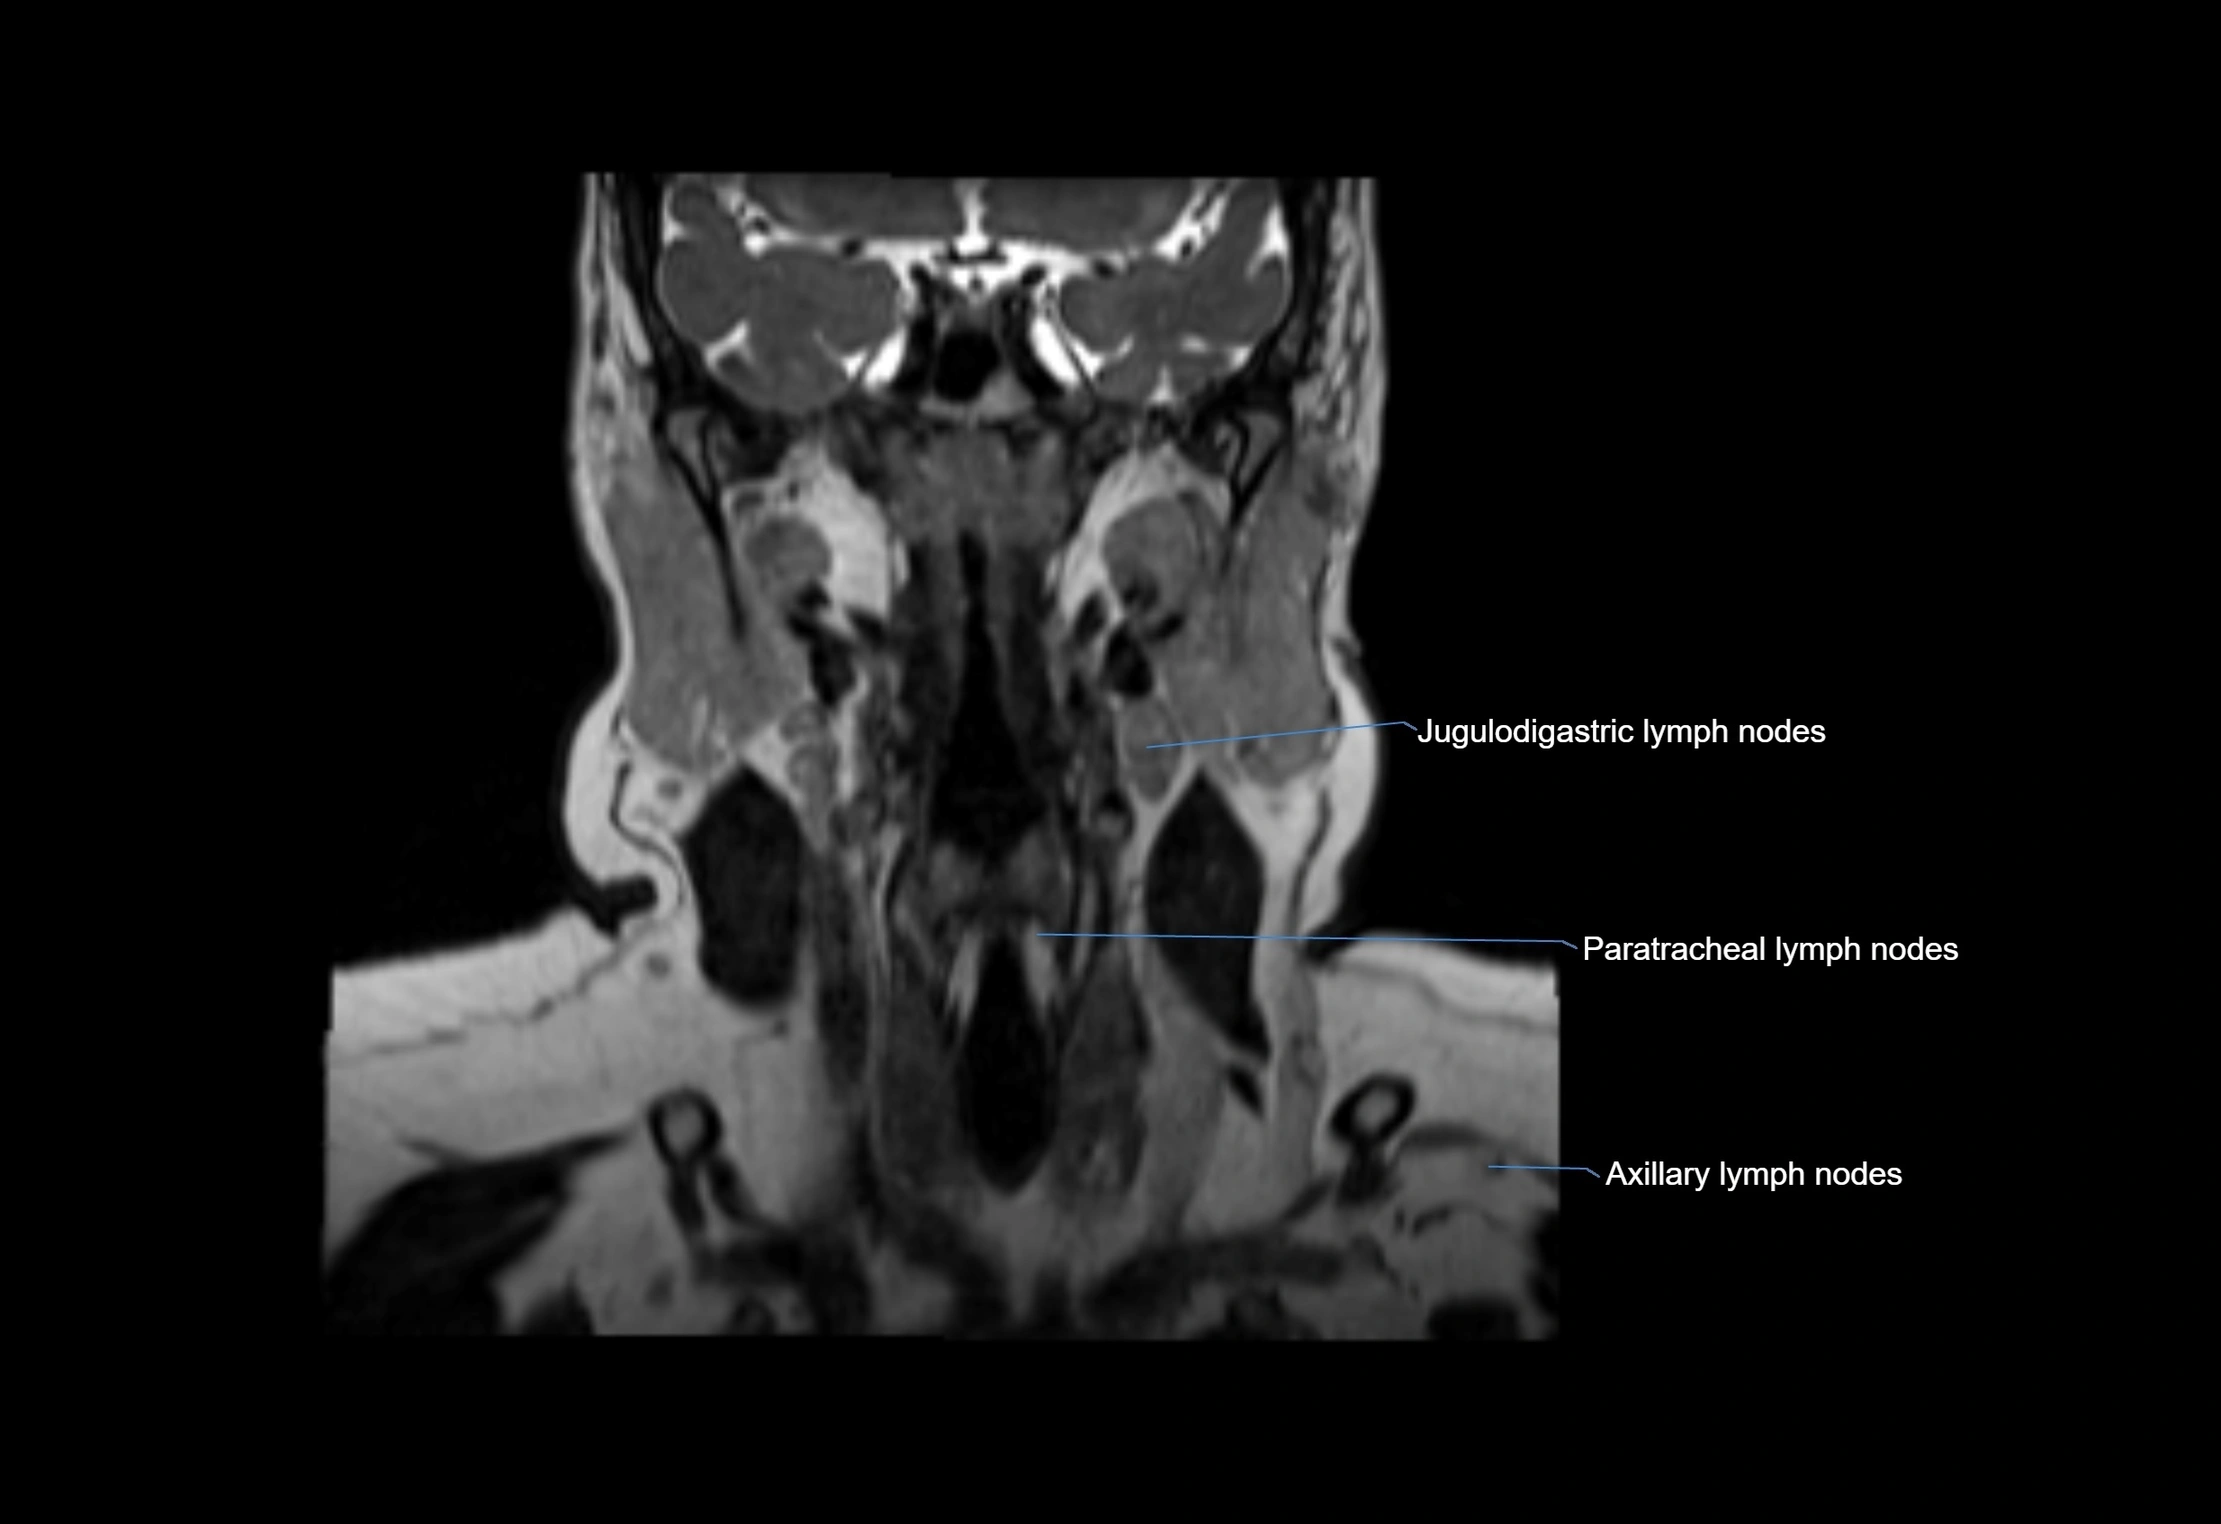

Location

• Found along primary lymph node chains, including preauricular, submandibular, parotid, and occipital regions

• Embedded in subcutaneous fat or superficial fascia, often lateral or posterior to primary nodes

MRI Appearance

T1-weighted images:

• Normal accessory nodes appear as small, oval hypointense to intermediate signal structures within subcutaneous fat

• Surrounded by hyperintense fat, enhancing contrast for visualization

• Pathological nodes may appear enlarged or rounded, sometimes with cortical thickening

T2-weighted images:

• Nodes show intermediate signal, with surrounding fat bright

• Useful for detecting edema, inflammation, or infiltration

• Fatty hilum may appear slightly hyperintense relative to cortex

MRI images

image